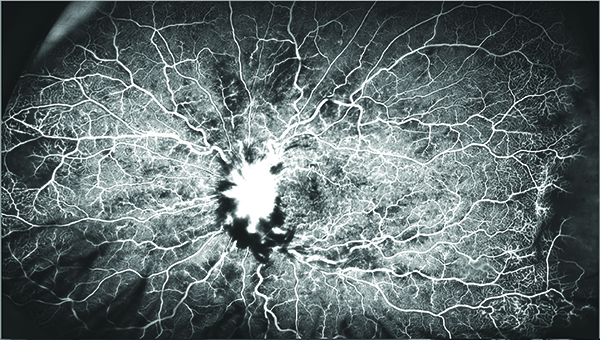

Angiografía panorámica